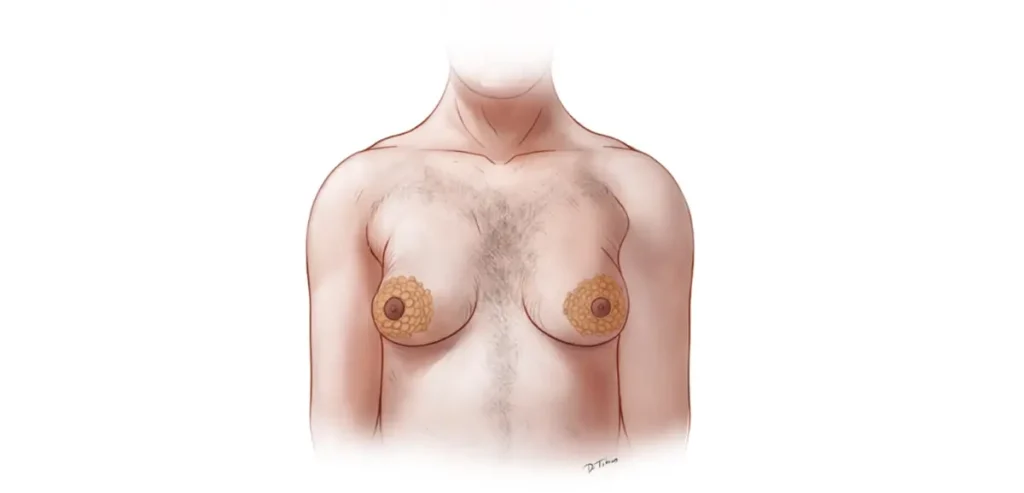

تزریق بوتاکس به واژن معمولاً به نواحی خاصی از عضلات واژن انجام میشود که درگیر انقباضات غیرارادی هستند. این نواحی شامل موارد زیر است:

- عضلات لواتور آنی (Levator Ani):

این عضلات در دیوارههای کناری واژن قرار دارند و نقش مهمی در انقباضات واژن ایفا میکنند. بوتاکس معمولاً به این عضلات تزریق میشود تا انقباضات غیرارادی کاهش یابد. - عضله پیسیس سیفونتر (Puborectalis):

این عضله نیز در ناحیه نزدیک به پرینه و مقعد قرار دارد و به کنترل انقباضات کمک میکند. تزریق بوتاکس به این ناحیه میتواند به کاهش درد و انقباضات کمک کند. - عضله بولبوکاورنوسوس (Bulbocavernosus):

این عضله در نزدیکی ورودی واژن قرار دارد و میتواند در صورت اسپاسم، باعث درد هنگام رابطه جنسی شود. بوتاکس میتواند به کاهش تنش در این عضله کمک کند.